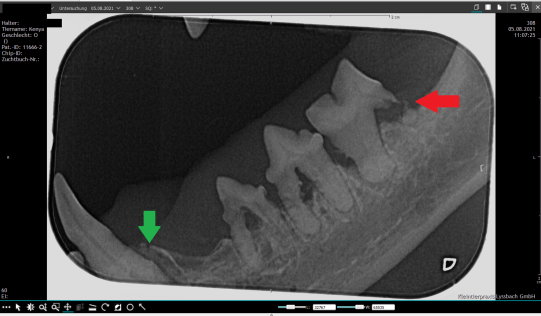

Im linken Unterkiefer lassen sich beispielsweise zwei verschiedene Krankheitsprozesse erkennen: Der Eckzahn (Zahn 304) weist eine Entzündung des Zahnfachs auf: Der Knochen um die Wurzel des Zahnes ist durch die chronische Entzündung stark aufgetrieben und der Zahn wackelt entsprechend (grüner Pfeil). Die hintere Wurzel des letzten Kauzahns (Zahn 309) ist zerfressen, hier handelt es sich um eine sogenannte FORL-Schädigung (roter Pfeil). Die beiden restlichen Zähne weisen Komponenten beider Erkrankungen auf.